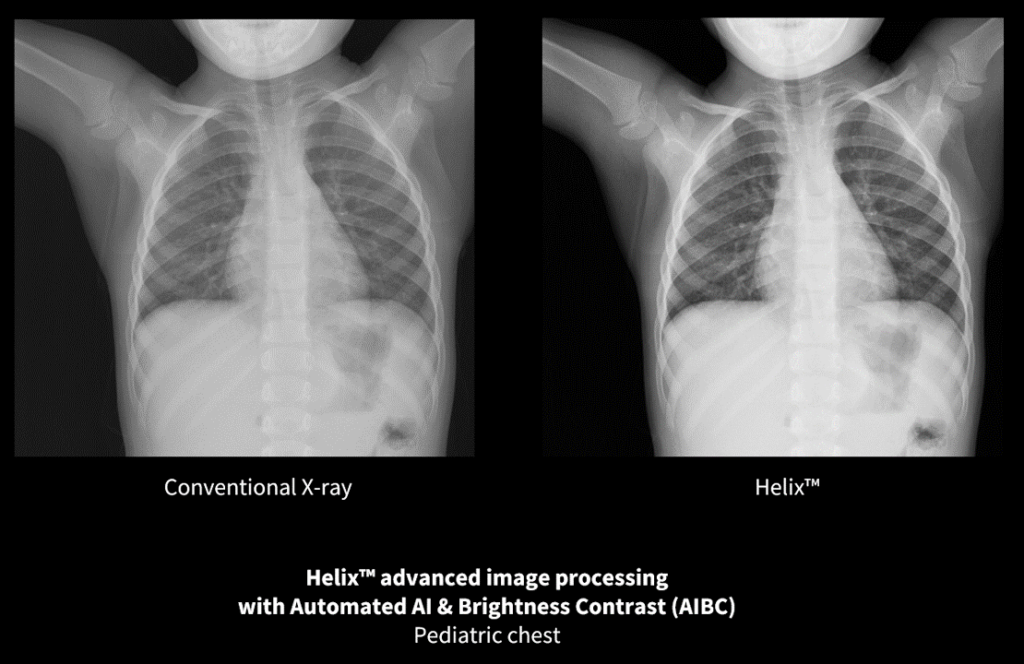

Helix Advanced Image Processing (X-ray) revolutionizes diagnostic imaging quality by consistently delivering images with appropriate detail, contrast, and latitude to enable radiologist to visualize key clinical details.

“Particularly in children in the ICU, who are sensitive to ionizing radiation… we were able to reduce the exposure required to achieve a diagnostic quality image… We were able to see through the mediastinum, to still see the bony details of the spine, which indicated that we had sufficient penetration but yet not burn out the details of the lung parenchyma and pulmonary vascular markings, and that really is an indication of a high-quality image.” – Dr. Nghia (Jack) N. Vo, MD Diagnostician-in-chief, Children’s Wisconsin; Chief of Pediatric Radiology, Medical College of Wisconsin [xi]